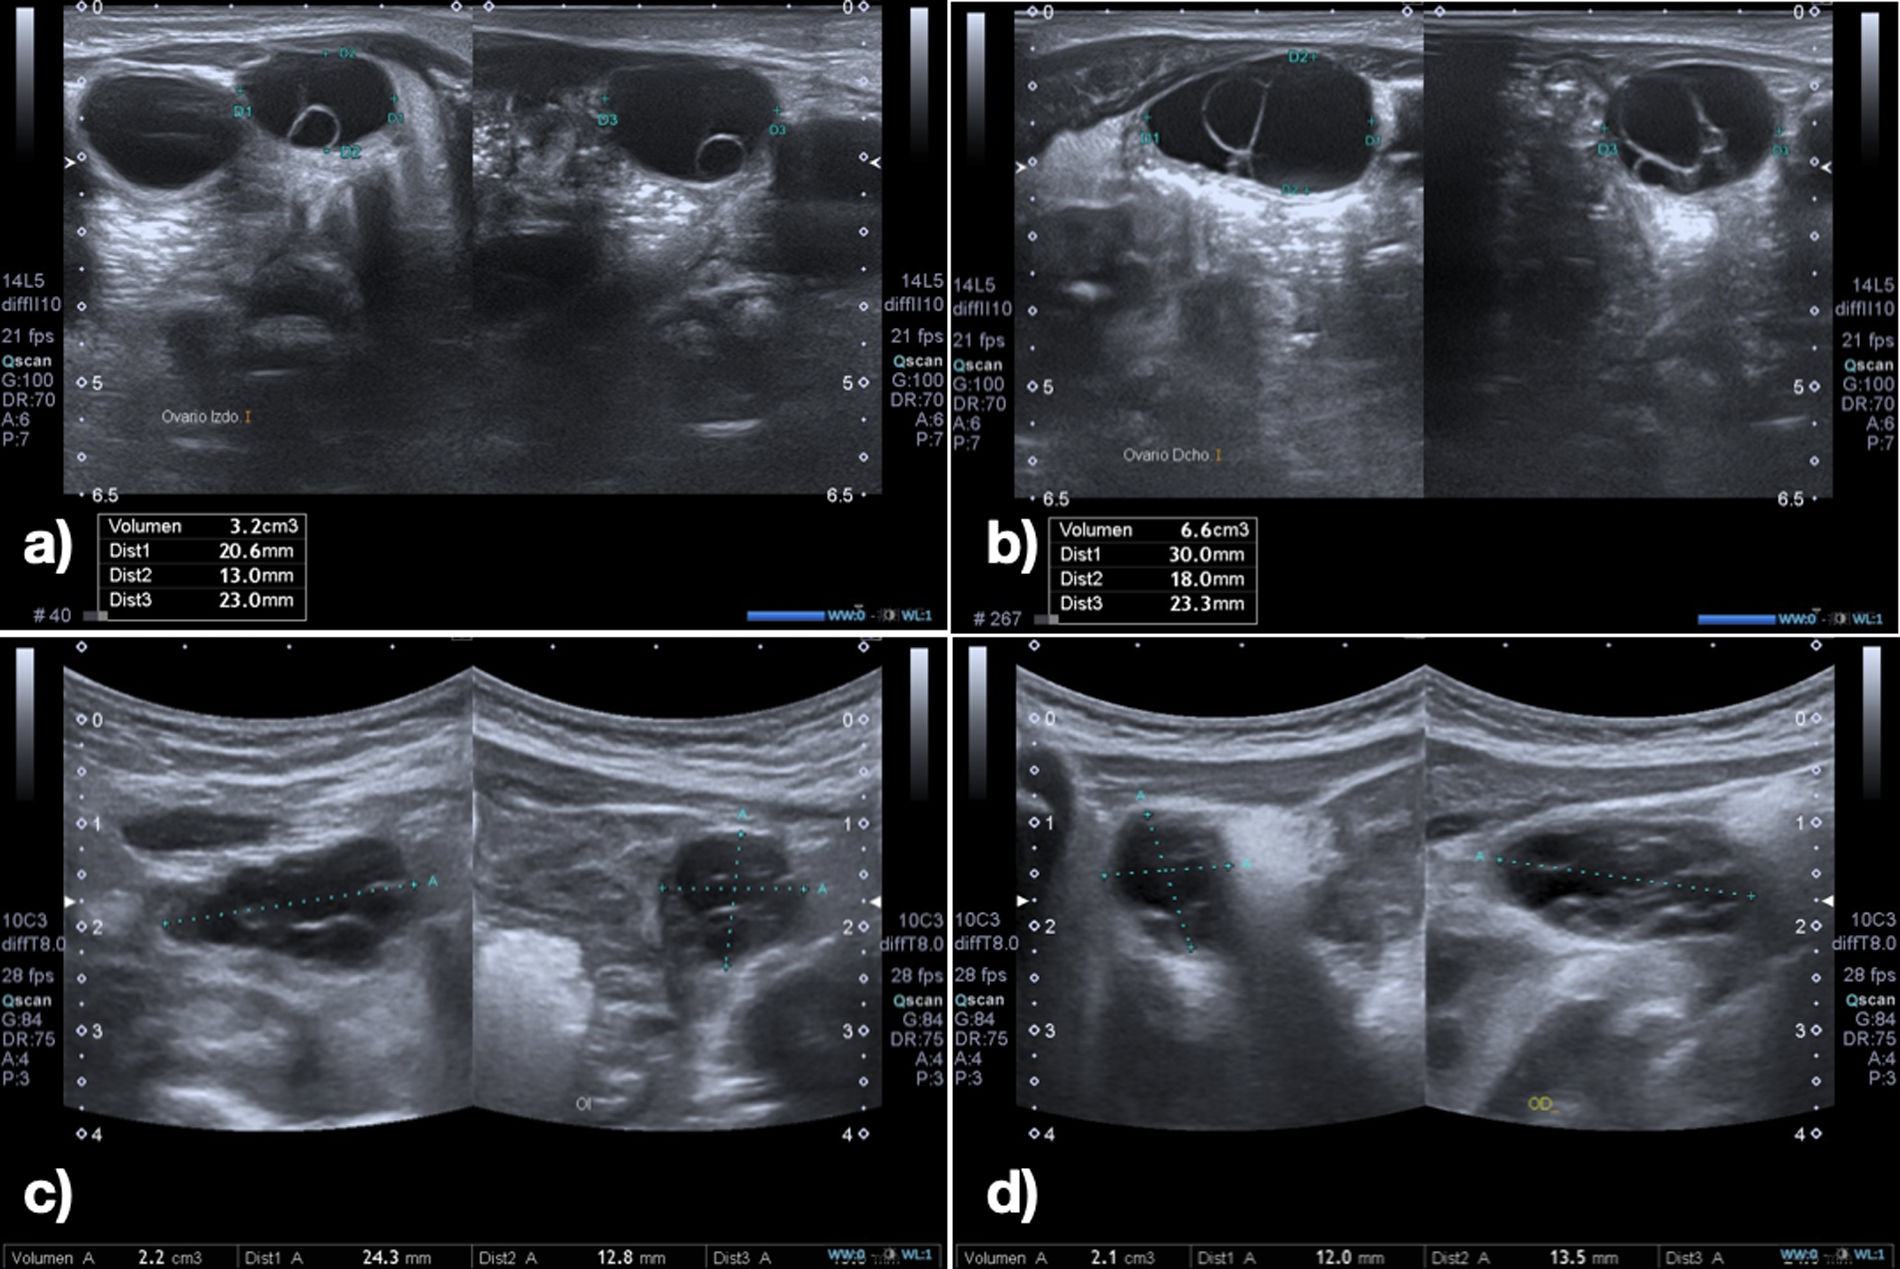

The blood work detected elevation of FSH, LH and estradiol levels (Fig. 2), and the abdominal ultrasound scan revealed ovarian enlargement and cystic lesions (Table 1).

| 3 months (36+3 weeks PMA) | 4 months (2 weeks CA) | 8 months (4 months CA) | |

| Left ovary ultrasound (cm3) | 3.2 | 2.2 | Not visualized |

| Right ovary ultrasound (cm3) | 6.6 | 2.1 | Not visualized |